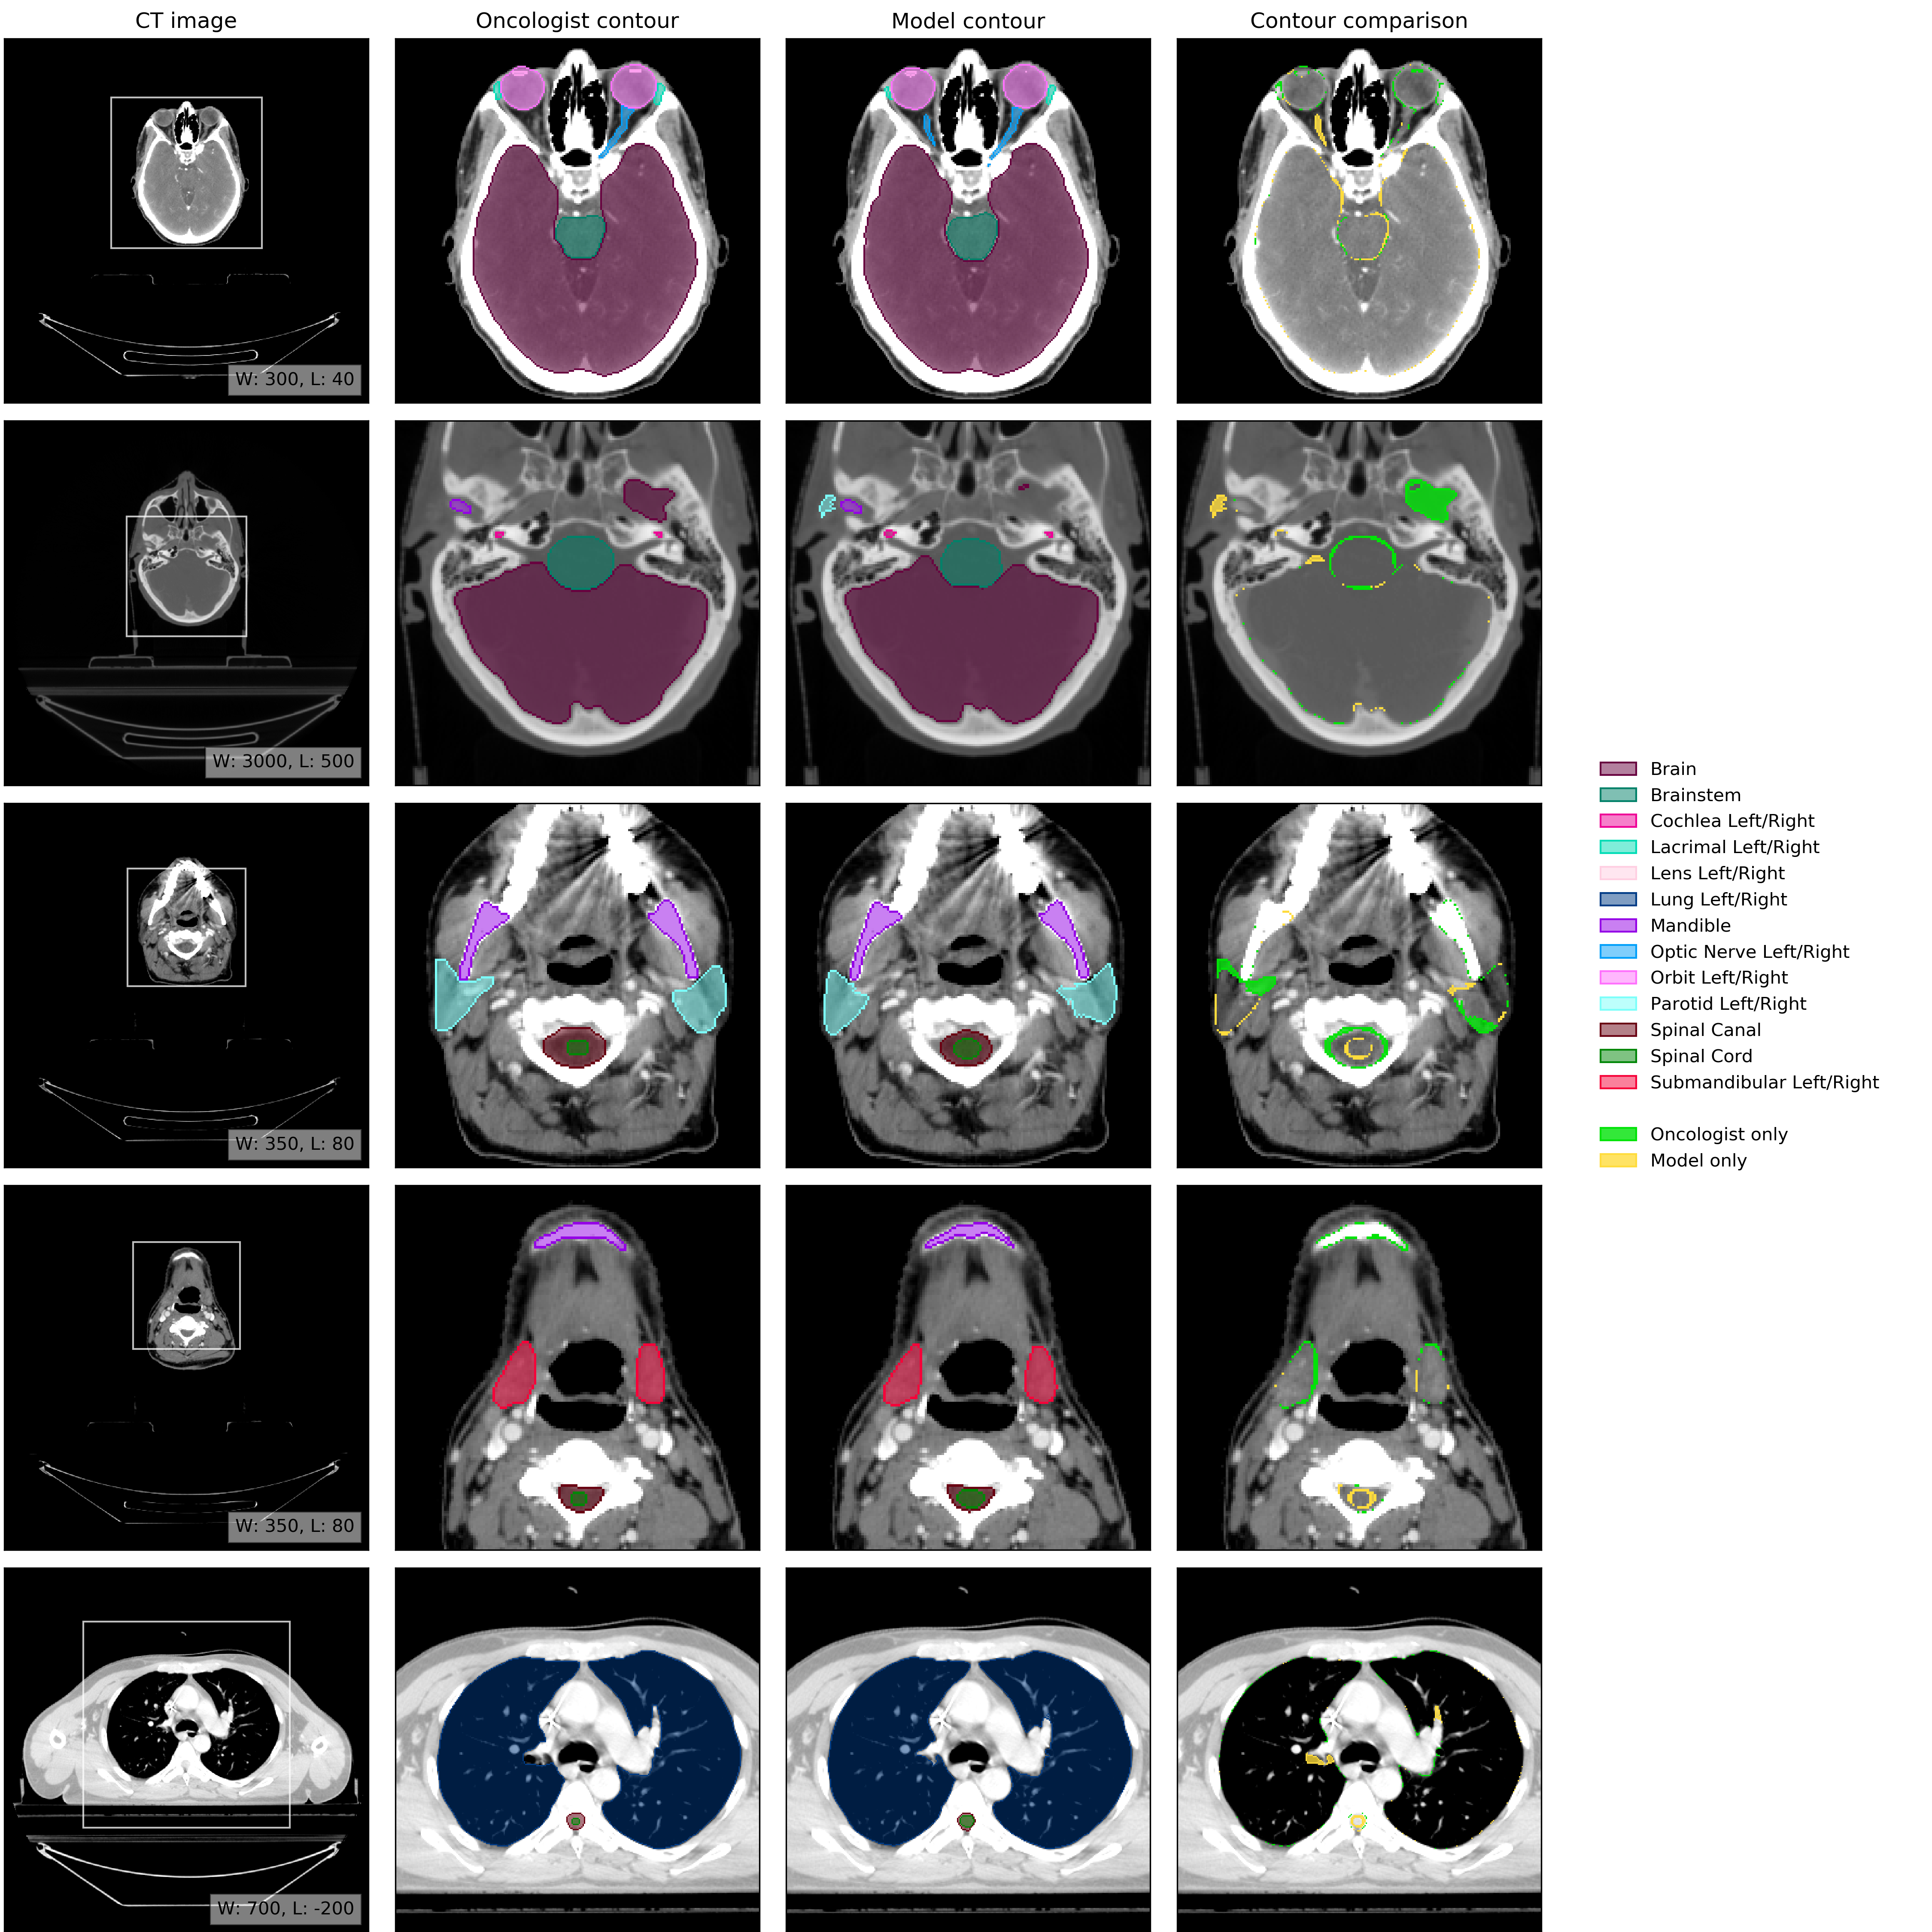

An example of model performance is shown in Fig. 2. We compare our performance (model vs oncologist) to radiographer performance (radiographer vs oncologist). For more information on dataset selection, inclusion and exclusion criteria for patients and OARs please refer to the Methods section.

Refer to caption

Figure 2: Example results. (CT image) Axial slices at five representative levels from the raw CT scan of a 55-59 year old male patient was selected from the UCLH dataset (patient UCLH-20) were selected to best demonstrate the OARs included in the work. The levels shown as 2D slices have been selected to demonstrate all 21 OARs included in this study. The window levelling has been adjusted for each to best display the anatomy present. (Oncologist contour) The ground truth segmentation, as defined by experienced radiographers and arbitrated by a head and neck specialist oncologist. (Model contour) Segmentations produced by our model. (Contour comparison) Contoured by Oncologist only (green region) or Model only (yellow region). Two further randomly selected UCLH set scans are shown in Fig. 12 and Fig. 13. Best viewed on a display.